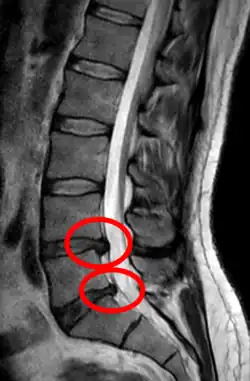

- Magnetic resonance imaging is the gold standard study for confirming a suspected LDH. With a diagnostic accuracy of 97%, it is the most sensitive study to visualize a herniated disc due to its significant ability in soft tissue visualization. MRI also has higher inter-observer reliability than other imaging modalities. It suggests disc herniation when it shows an increased T2-weighted signal at the posterior 10% of the disc. Degenerative disc diseases have shown a correlation with Modic type 1 changes. When evaluating for postoperative lumbar radiculopathies, the recommendation is that the MRI is performed with contrast unless otherwise contraindicated. MRI is more effective than CT in distinguishing inflammatory, malignant, or inflammatory etiologies of LDH. It is indicated relatively early in the course of evaluation (<8 weeks) when the patient presents with relative indications like significant pain, neurological motor deficits, and cauda equina syndrome. Diffusion tensor imaging is a type of MRI sequence used for detecting microstructural changes in the nerve root. It may be beneficial in understanding the changes that occur after herniated lumbar disc compresses a nerve root, and might help in differentiating the patients that need surgical intervention. In patients with a high suspicion of radiculopathy due to lumbar disc herniation, yet the MRI is equivocal or negative, nerve conduction studies are indicated.[44] T2-weighted images allow for clear visualization of protruded disc material in the spinal canal.

A rather severe herniation of the L4–L5 disc -

Example of a herniated disc at L5–S1 in the lumbar spine